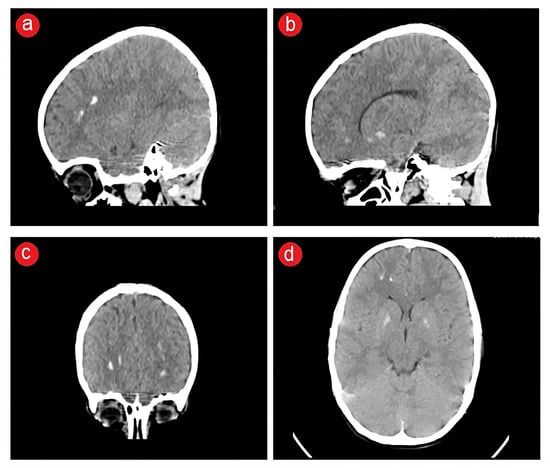

2.3. Biological and Paraclinical Assessment